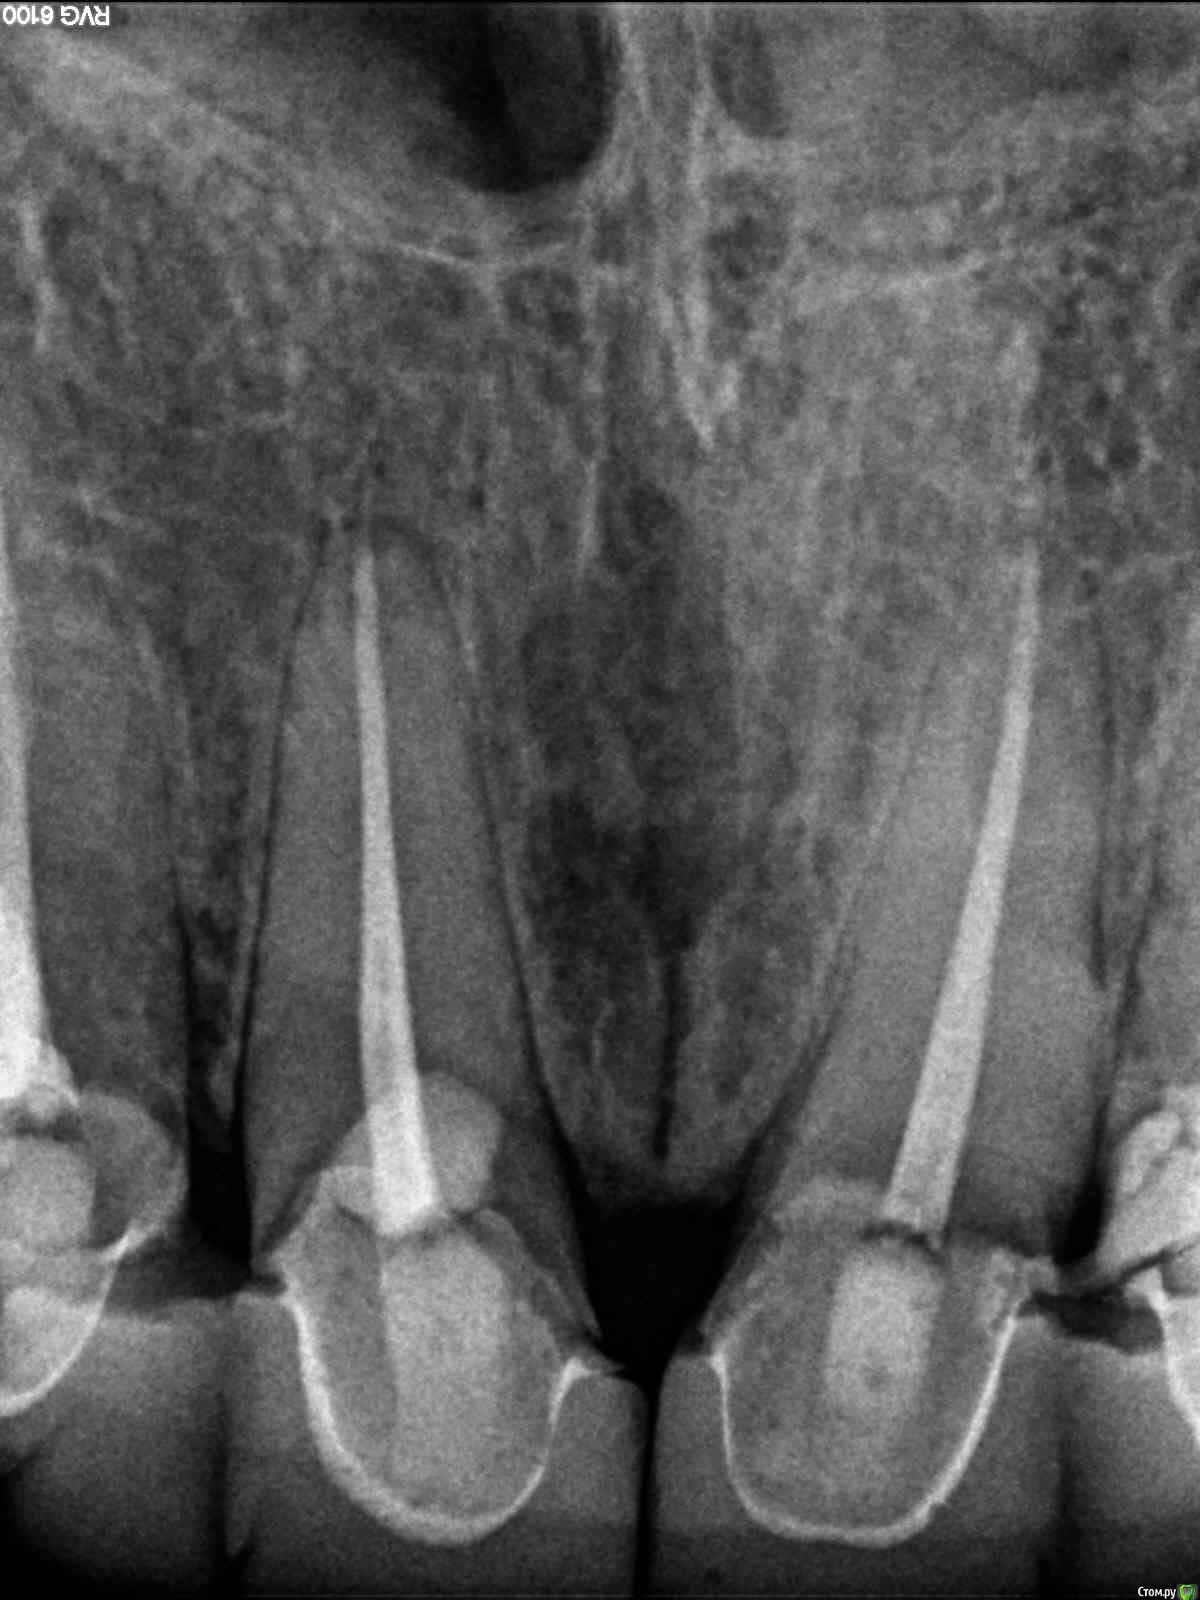

lazzal Опубликовано 29 октября, 2015 Поделиться Опубликовано 29 октября, 2015 (изменено) Уважаемые ортопеды, дайте пожалуйста совет и свои рекомендации. в 2012 г была установлена конструкция на передние верхние зубы из безметалловой керамики. 2 мини моста резец-клык справа и слева. устанавливались на свои абсолютно здоровые зубы, предварительно депульпированные, так сделать предложил врач, чтоб была типа "голливудская улыбка". у меня от природы отсутствовали двойки с обоих сторон, правда зазор был не большой, но все равно смотрелось не очень, клыки сразу бросались в глаза. так вот, врач мне сказал, что конструкция прослужит 20 лет, а у меня через 2,5 года начались проблемы. начали чернеть кромки вдоль конструкции с внутренней стороны. терапевт диагностировал кариес. ортопед сказал снимать не надо, можно их изнутри немного сточить, пролечить кариес и запломбировать. так и сделала. но пломбы теперь вылетают каждые 3-4 месяца. врач который лечит, сделал снимки и сказал, что там с правой стороны между резцом и клыком гниет корень и надо конструкцию снимать, а то потеряем корень. мой ортопед же говорит, что все нормально - пусть стоят, надо лучше пломбировать. снимать я сама не хочу конечно. но корень дороже. кто из них прав и что мне делать? еще сложность в том, что конструкция похоже крепится на какой-то супер клей и просто так ее сбить или спилить не получится (проговорился мой ортопед). я не представляю как это все может выглядеть, стешут по самые десны и сделают вкладки? очень бы этого не хотелось, т.к. хотелось бы этот вариант оставить про запас, т.к. потом, если что случись - олько имплантация и то, если это будет возможно. Посмотрите снимки и подскажите, что можно сделать им почему такой короткий срок службы? как смог развиться кариес? Так же прилагаю и панорамный снимок, возможно вы увидите и укажете мне на еще какие-то проблемы с зубами или деснами, на которые стоит обратить внимание. С уважением и благодарностью, я. Изменено 29 октября, 2015 пользователем lazzal Ссылка на комментарий

lazzal Опубликовано 30 октября, 2015 Автор Поделиться Опубликовано 30 октября, 2015 Посмотрите пожалуйста в каком состоянии зуб под коронкой, возможно ли его спасти? Ссылка на комментарий

Bier Опубликовано 30 октября, 2015 Поделиться Опубликовано 30 октября, 2015 В плачевном состоянии, его сохранение под вопросом 1 Ссылка на комментарий